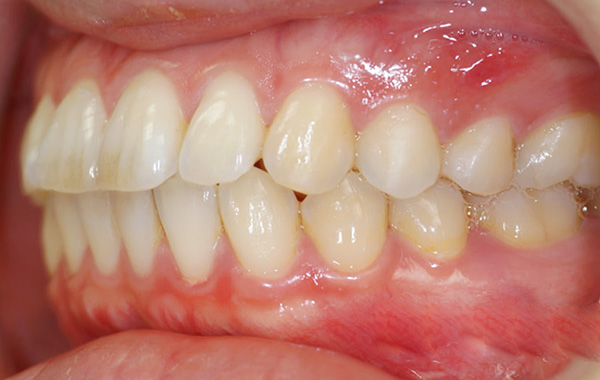

A dentição é muito sensível a quaisquer alterações nela, portanto, mesmo se o médico tratou a pulpite de acordo com todas as regras e com danos mínimos no tecido dentário, desconforto e até dor ao morder devido a um preenchimento são possíveis por algum tempo - isso se refere principalmente a restaurações na mastigação molares de superfície.

Após o tratamento, os dentes às vezes fecham um pouco diferente, não como de costume. A sensação de desconforto de um novo preenchimento pode normalmente ser de 5 a 7 dias.

Se o paciente sentir desconforto por mais tempo, se o dente interferir com a mordida e houver uma sensação de que é mais alto que o resto dos dentes, sem a intervenção de um médico, isso pode levar a vários problemas - a partir do afrouxamento do próprio dente (uma vez que ele tem uma carga aumentada) e terminando com problemas na articulação temporomandibular.